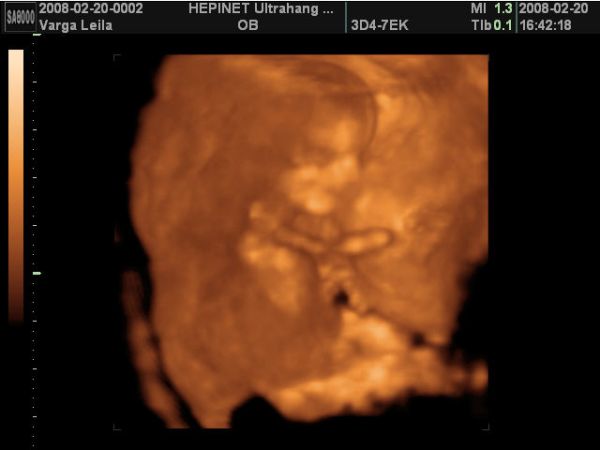

A lába között volt a köldökzsinór, és hát eléggé ficánkolt is, úgyhogy csak egyszer láttunk valamit, mikor terpesztett 2D-ben. A nő azt mondta, hogy olyan fiúsnak látszik, de még nem mer biztosat mondani. Szerintem is az lesz, mert én is úgy érzem. De azért a 18. hetin már remélem jól fog látszani.